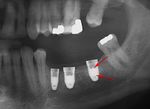

Bone loss (peri-implantitis) on implants over 7 years in a heavy smoker

Fracture of abutment screws (arrow) in 3 implants required removal of the remainder of the screw and replacement.